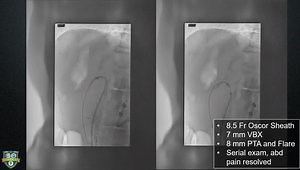

Now That We Have Passed the Occluded SFA, What Are the Best

…

Technical Tips for Complex SMA Recanalization and Stenting

Stenting the SMA from start to finish